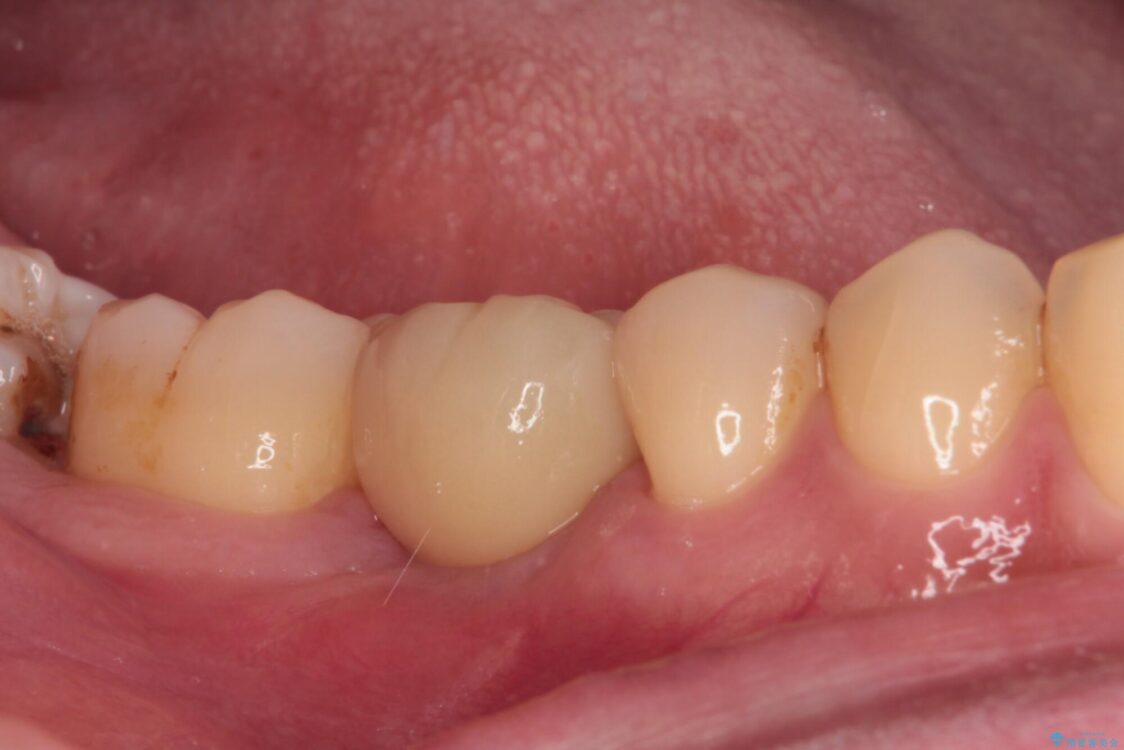

治療後

• 空いている時間を利用して通院 奥歯のインプラント治療 治療後画像